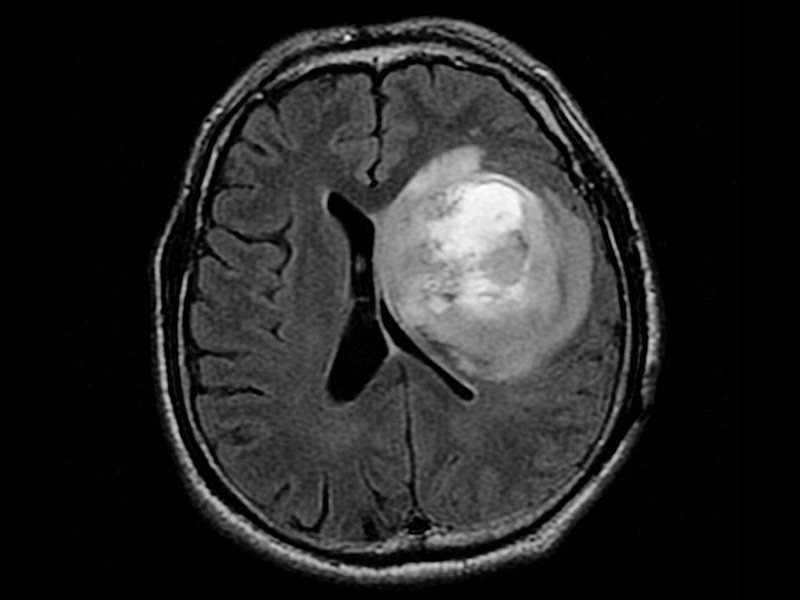

胶质母细胞瘤是一种高度恶性的脑肿瘤,起源于神经系统中的支持细胞--星形胶质细胞。正常情况下,星形胶质细胞负责多种角色,包括为神经元提供营养,维持血脑屏障,调节神经传递(神经元之间的交流方式)。胶质母细胞瘤通常发生在大脑半球,但也可能发生在大脑或脊髓的几乎任何区域。考虑到肿瘤细胞增殖迅速,并由广泛的血管网络支持,它们具有恶性。胶质母细胞瘤是星形细胞瘤中较恶性的一种,也是更广泛的一种胶质瘤--起源于胶质细胞的肿瘤。这是因为星形胶质细胞是一种胶质细胞。因此,胶质母细胞瘤也可称为“IV级胶质瘤”。

胶质母细胞瘤是一种较具侵袭性的脑癌,是一种原发性的脑癌,会影响大脑中被称为胶质瘤的不同细胞。这种侵袭性癌症的治疗通常很困难,手术和放射治疗往往不能治愈这种癌症。这种癌症通常生长迅速,初期可能没有任何症状。只有当肿瘤变大且更难治疗时,才会出现这些症状。在晚期,大脑功能异常,随着肿瘤的快速生长,这种情况很快就会致命。在一些患者中,较初的治疗可能有助于暂时减缓疾病的进展,但在大多数患者中,癌症会复发,然后出现严重的复发和生长。